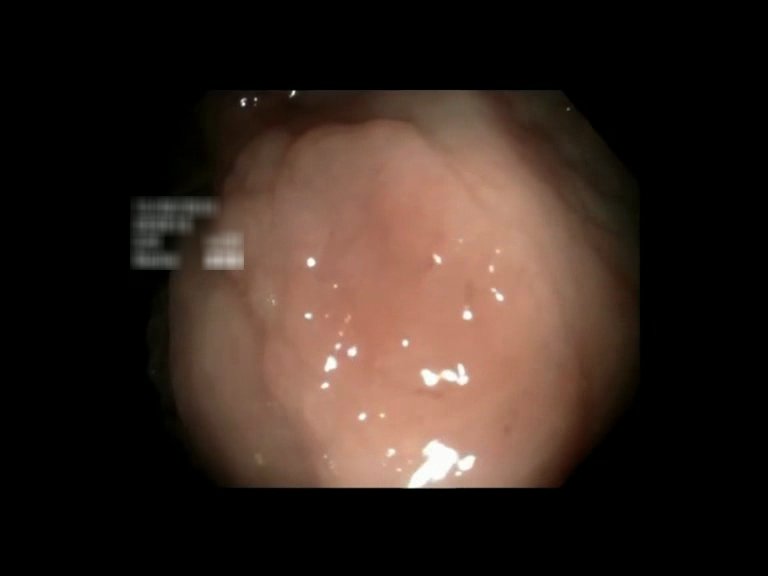

| Lesion | White Light Frame | NBI Frame | White Light Video | NBI Video | Camera Calibration |

| hyperplasic_01 |  |

|

WL.mp4 | NBI.mp4 | cam.xml |